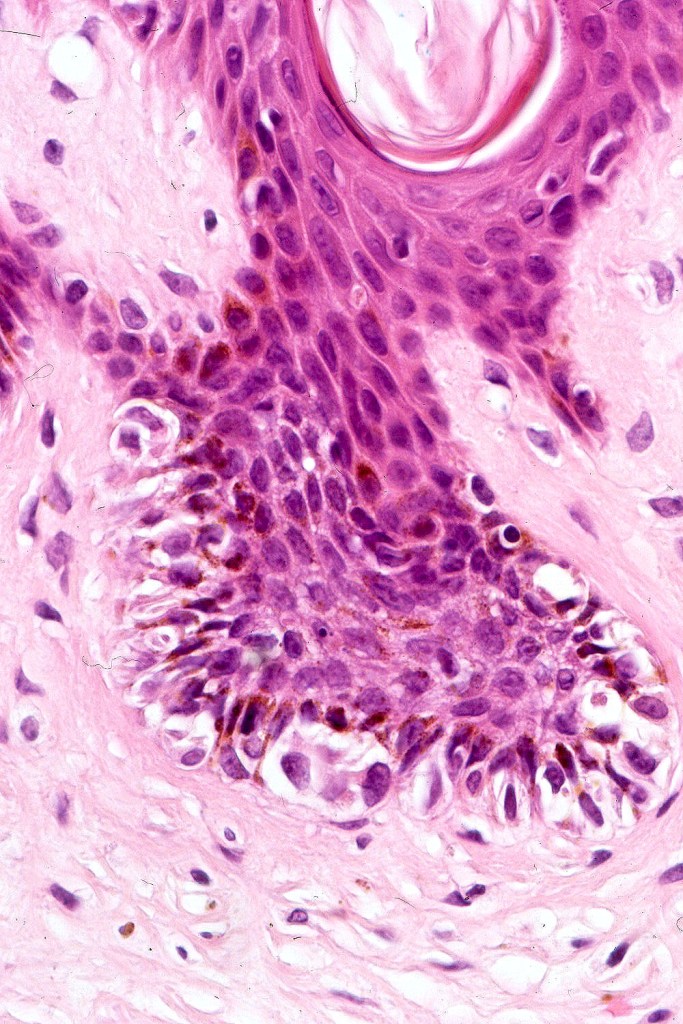

•Architectural disorder- lentiginous and nested, nests abnormally located (at the sides of the rete ridges & overlying the dermal papillae in addition to the tips of the rete ridges rather than solely occupying the tips of the rete ridges as is seen in banal nevi), horizontal orientation & bridging between junctional nests (this should not be confused with bridging between adjacent rete ridge squamous epithelium)

•Abnormal fine pigmentation (dusty)

•Host response- eosinophilic & lamellar fibroplasia, increased vascularity, lymphocytic infiltration & pigment incontinence

•In compound lesions, the nest size should be smaller than the junctional ones and the degree of atypia the same or less